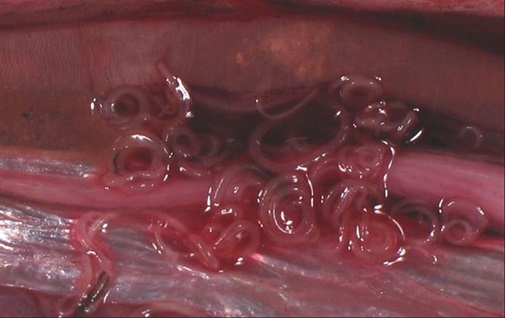

Водные обитатели являются промежуточными хозяевами для паразитов. Их яйца, попадая от инфицированных особей с фекалиями в воду, при благоприятных условиях существуют долгое время. Членистоногие или мелкие рыбешки заглатывают их вместе с песком и илом. Попадая в организм нового хозяина, паразиты начинают расти и размножаться. Более крупные, хищные виды инфицируются, питаясь зараженными особями. Паразиты, попадая к хозяину, поселяются не только в пищеварительном тракте, но и в мясе, икре, молоках, жабрах или под чешуей.

Не смотря на то, что перечень гельминтов, которые не передаются человеку достаточно широкий, большинство глистов успешно приживаются и размножаются у людей. Наиболее опасные разновидности – это сосальщики, ленточные и круглые черви.